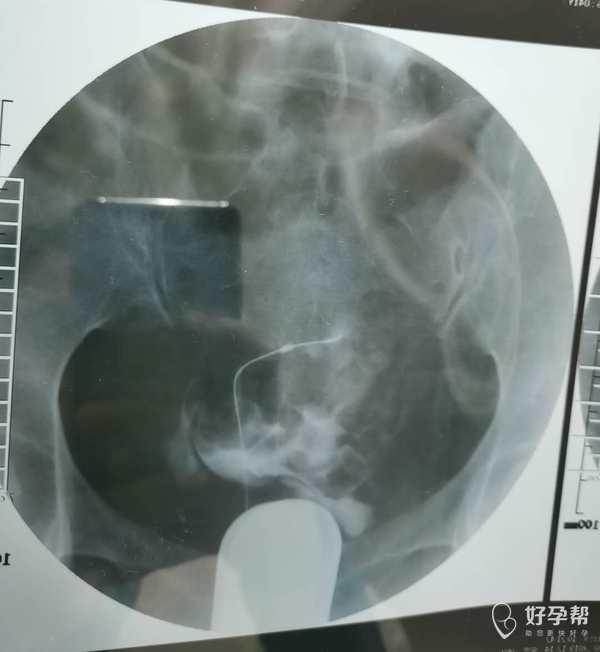

我这个是做了输卵管介入手术,请问输卵管是通了

你的片子提示双侧输卵管不通,未孕4年,合并腺肌症和腺肌瘤,建议你直接试管婴儿助孕。试管前不需要宫腹腔镜检查。